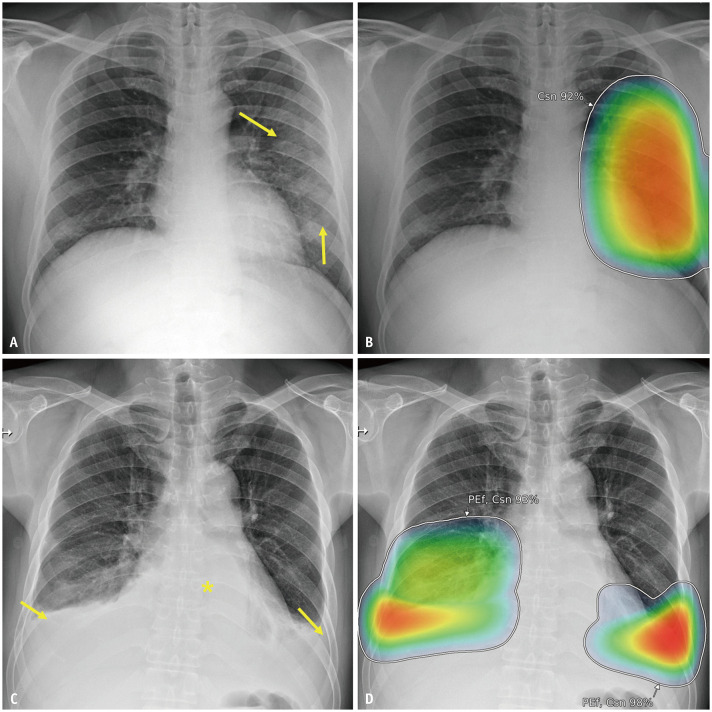

Materials and methods: This secondary analysis of a previous clinical trial included patients who visited the ED with symptoms suggestive of acute cardiopulmonary disease and underwent chest radiography between June 2020 and December 2021. All patients underwent triage upon arrival at ED according to the Korean Triage and Acuity Scale (KTAS). The CXRs were retrospectively analyzed using a commercial AI (Lunit INSIGHT CXR, version 3.1.4.1) capable of detecting seven abnormalities on a single frontal CXR. The predictive performance of the AI analysis for major adverse cardiopulmonary events (any among hospitalization, ED revisits, and death in the ED due to acute cardiopulmonary disease) was compared with that of the KTAS using the area under the receiver operating characteristic curve (AUC). Multivariable (the AI analysis result and KTAS level) logistic regression analysis was conducted to investigate whether the AI analysis result was an independent predictor of the events and whether the combination of the AI analysis and KTAS has additional merit.

Results: Among 3576 patients (1966 males; mean age, 64 years), 1148 (32.1%) experienced major adverse cardiopulmonary events. AI analysis of CXRs outperformed the KTAS in predicting these events (AUC, 0.795 vs. 0.610; P < 0.001). The AI analysis result was an independent predictor of these events after adjusting for the KTAS level (adjusted odd ratios of 1.032 and 6.913 for every 1% increase and ≥15%, respectively, in the AI probability score; P < 0.001). The combination of the AI analysis and KTAS showed an AUC that was higher than that of the KTAS alone (0.799; P < 0.001) and in-par with that of the AI analysis only (P = 0.187).

Conclusion: AI analysis of CXRs showed greater accuracy than the KTAS did in predicting major adverse cardiopulmonary events in patients visiting the ED with acute cardiopulmonary symptoms. AI analysis may enhance the efficacy of patient triage in the ED.